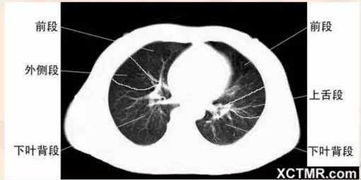

医院CT检查

肺结节是指肺实质内直径小于3厘米的圆形或类圆形阴影,多数为良性,但也可能是早期肺癌的表现。